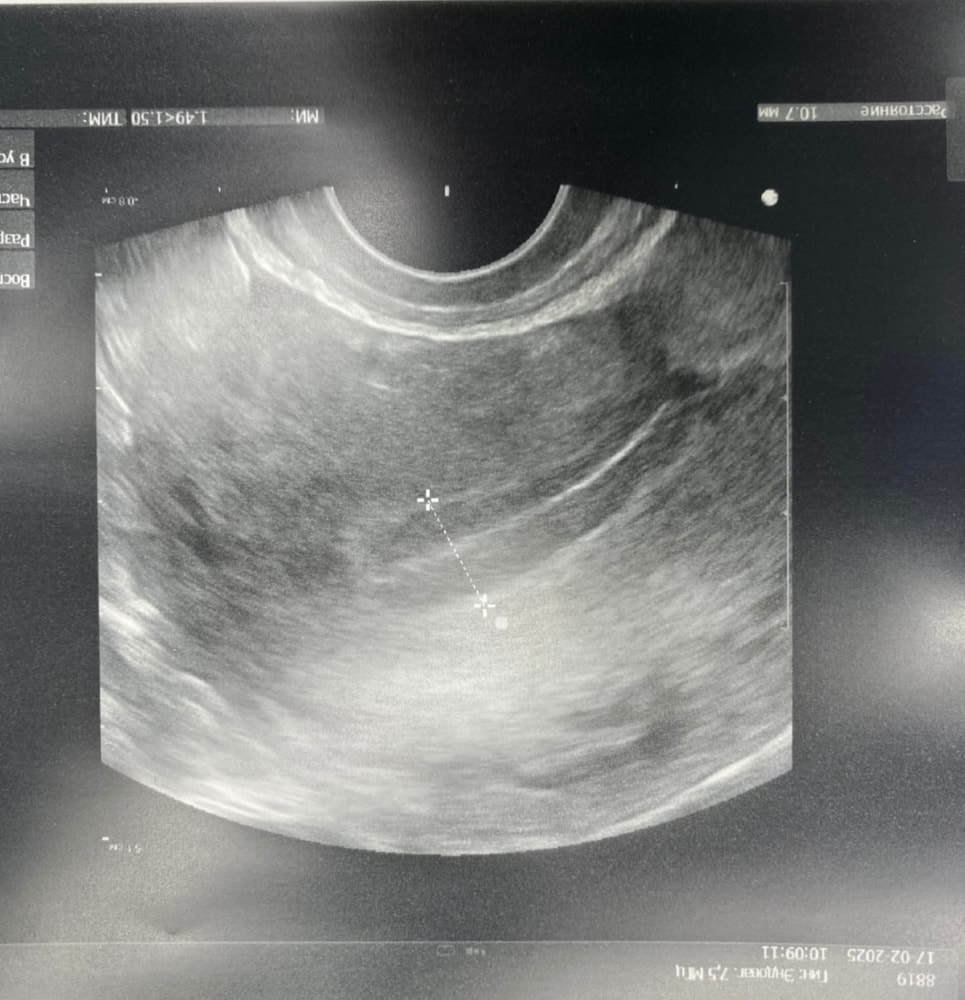

Вот мой эндик хороший до эсрогенов и с жидкостью с приемом прогинова